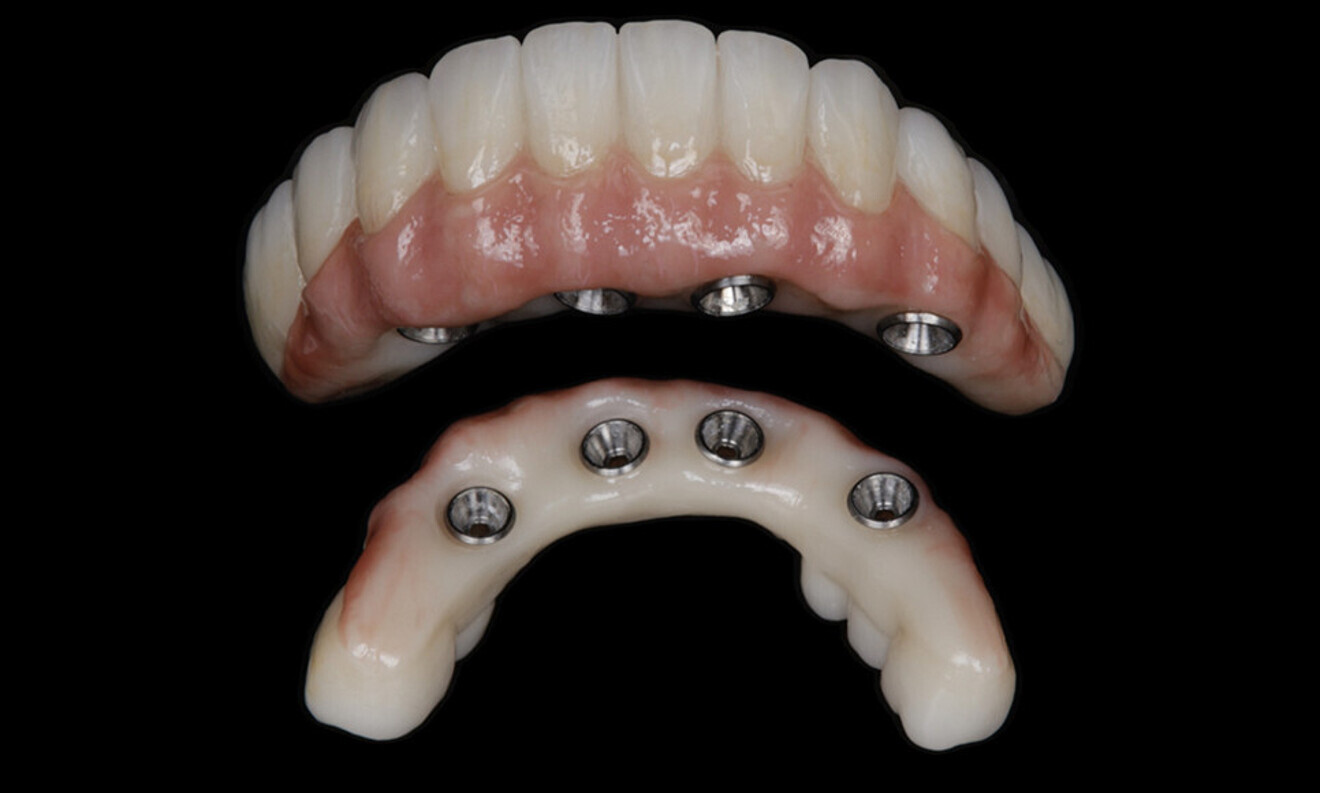

After a healing period of five months and successful osseointegration, the process for the definitive restorations was initiated. The chosen material was milled monolithic zirconia, and Variobase final abutments was used, placed on the screw-retained abutments to ensure excellent stability and retention of the definitive restorations (Figs. 69–75).

Figs. 69–75: The definitive restorations were fabricated after a five-month healing period